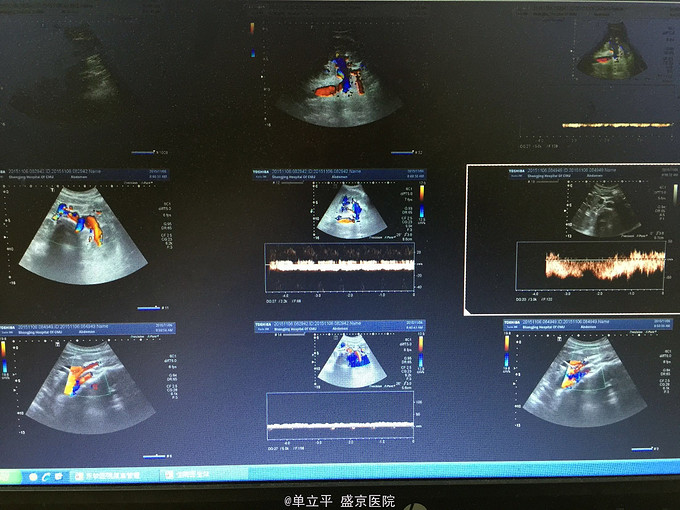

查体:瘦高体型,170cm,50kg。左肾区叩痛阳性. 辅助检查:CT提示左肾盂哪充盈缺损 尿查瘤细胞隐形 超声检查提示:肾静脉受压改变,符合胡桃夹综合征

胡桃夹综合症 处理:保守治疗3个月,增加体重